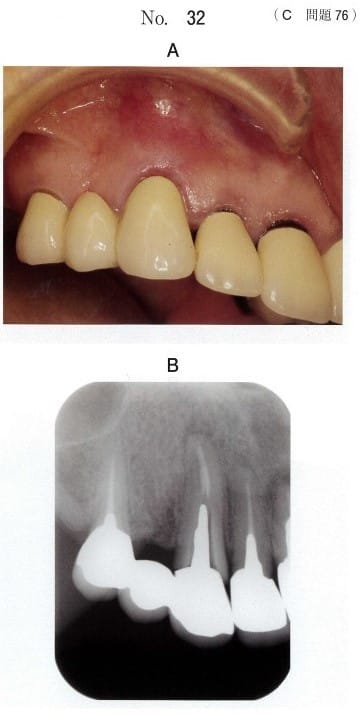

61歳の女性。上顎右側犬歯の歯肉腫脹を主訴として来院した。

1か月前から自覚していたがそのままにしていたという。

初診時の口腔内写真(別冊No.32A)とエックス線画像(別冊No.32B)を別に示す。

原因として考えられるのはどれか。2つ選べ。

a 歯根破折

b 根尖性歯周炎

c 歯肉縁下歯石

d 頬小帯付着異常

e 二次性咬合性外傷

| 問題番号:118C-76 | 61歳の女性。上顎右側犬歯の歯肉腫脹を主訴として来院した。 初診時の口腔内写真(別冊No.32A)とエックス線画像(別冊No.32B)を別に示す。

原因として考えられるのはどれか。2つ選べ。 a 歯根破折

正解:ab |

正答率:84.9% | |